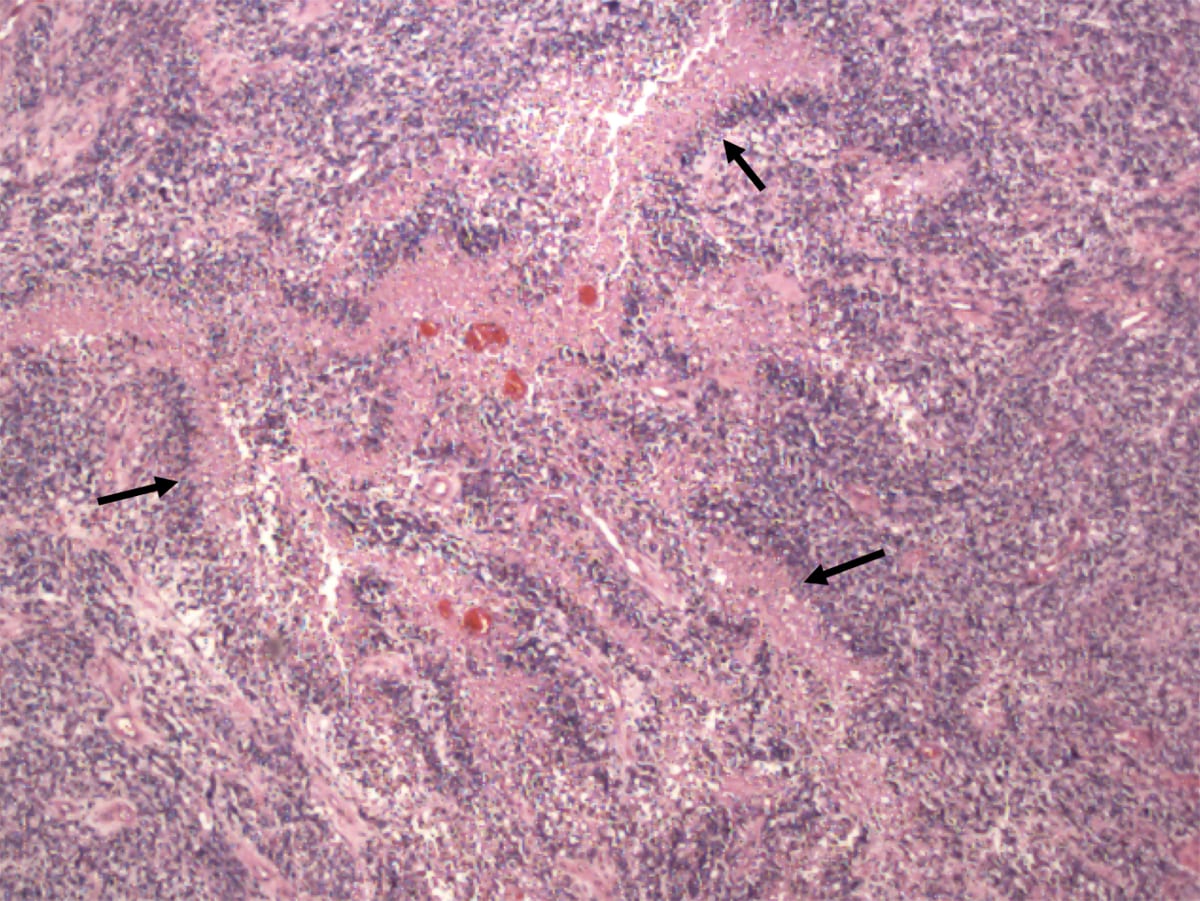

Микрофотографии гистологии глиобластомы головного мозга